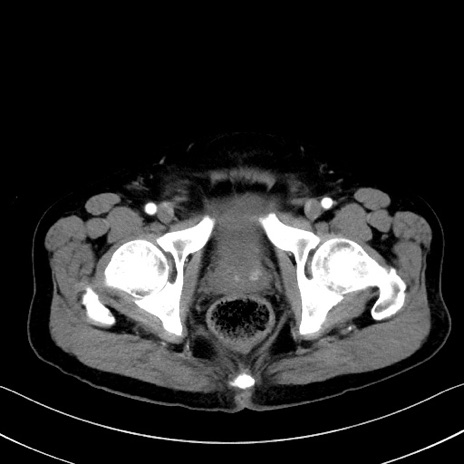

症例35(横断像)

【症例】70歳代 男性

【主訴】腹部膨満、嘔吐

【現病歴】昨日より腹部膨満感出現。本日増悪し、仙痛出現。嘔吐あり、受診。

【既往歴】糖尿病、胆摘後

【身体所見】BP 149/80mmHg、HR 74/min、BT 35.9℃、腹部:膨満、軟、圧痛なし。腸雑音減弱あり。上腹部正中切開瘢痕あり。

【データ】WBC 13500、CRP 1.72